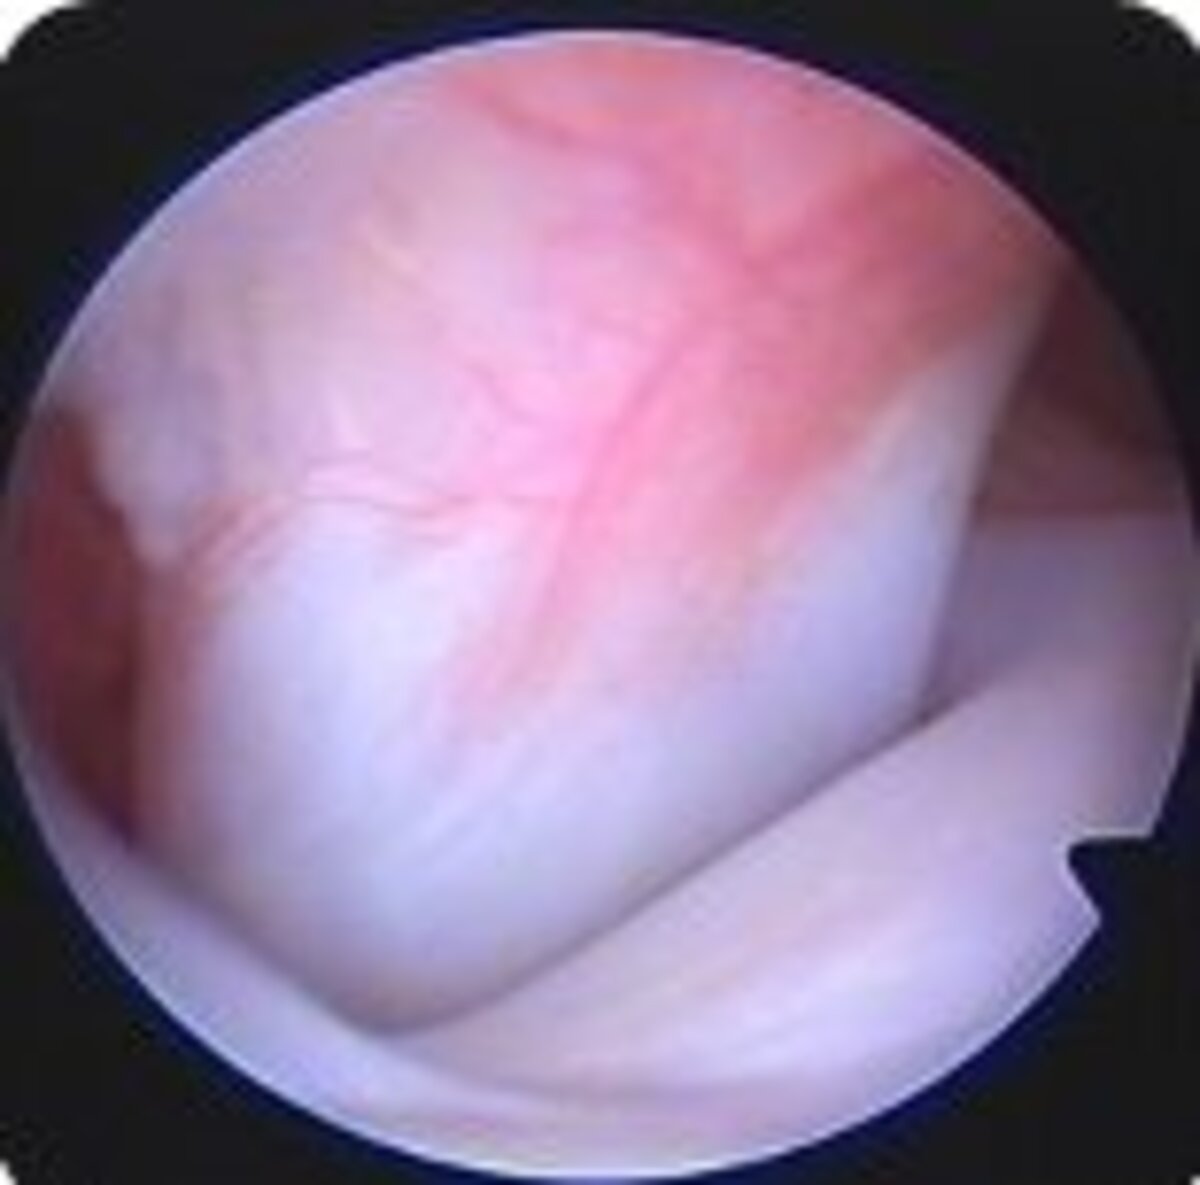

Die Diagnose „vorderer Kreuzbandriss“ kann meist bei der klinisch orthopädischen Untersuchung gestellt werden. Eine abnorme Verschieblichkeit im Kniegelenk zwischen Ober- und Unterschenkel ist dabei beweisend. Man nennt das Ergebnis dieser Untersuchung „positiven Schubladen- und Tibiakompressionstest“. In unklaren Fällen, also bei klinisch nicht instabilem Kniegelenk, bei denen weiterhin der Verdacht auf einen Kreuzbandriss besteht, werden zur definitiven Diagnosestellung bildgebende Verfahren verwendet. Dabei kommen Röntgen, Kernspintomographie (MRT) und Arthroskopie (Kniegelenkspiegelung) zum Einsatz.